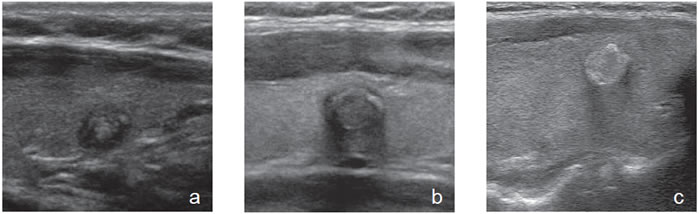

3. Ecogenicidad

El parénquima tiroideo normal es de mayor ecogenicidad que los músculos pre-tiroideos. Los nódulos tiroideos pueden ser de menor ecogenicidad que el tejido glandular (hipoecogénicos), de ecogenicidad similar (isoecogénicos) o de mayor ecogenicidad (hiperecogénicos). La ecogenicidad de un nódulo se refiere al nivel de blanco, gris y negro que muestran en la imagen ecográfica (Figura 3a, b y c). La mayoría de los carcinomas papilares (75%-85%) son hipoecogénicos13. La hipoecogenicidad es un signo sensible pero inespecífico, ya que un 30% a 50% de los nódulos benignos14 también son hipoecogenicos (Figura 4). Sin embargo, si la hipoecogenicidad es acentuada (menor que la de los músculos pretiroideos), aumenta la sospecha de carcinoma (Figura 5). Los nódulos hiperecogénicos o isoecogenicos tienen mayor grado de asociación con lesiones hiperplásticas o foliculares benignas, y en mucho menor proporción con el cáncer papilar. Los nódulos puramente quísticos se definen como anecogénicos independiente de si muestran uno que otro fino septo aislado. Cuando el coloide se espesa, se forman microcristales que se ven como focos hiperecogénicos que contrastan con el fondo de coloide anecogénico, y generan un artefacto ultrasonográfico por reverberación, que produce una imagen posterior similar a la cola de un cometa (Figura 2a). La presencia de estos focos hiperecogénicos en un nódulo quístico indican la presencia de abundante coloide y se correlaciona con benignidad; prácticamente están ausentes en un nódulo maligno15.